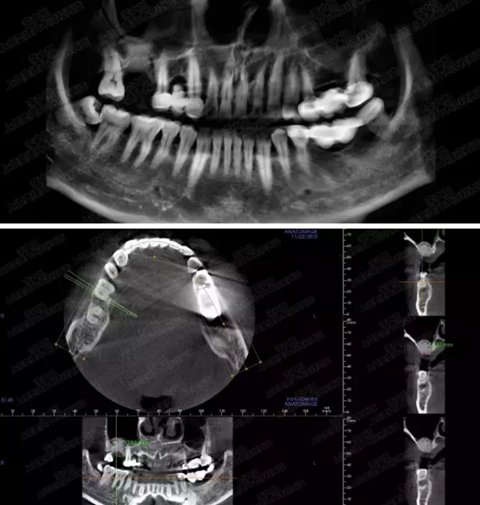

病例一

上頜竇多分隔3mm

05.png

提升8mm

06.png

07.png

修復(fù)時根尖片

08.png

09.png